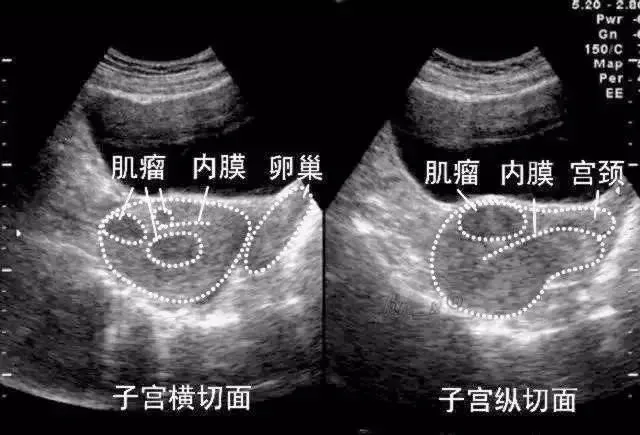

●二维超声表现:子宫增大、形态失常,肌壁间肌瘤和粘膜下肌瘤子宫常均匀增大;浆膜下肌瘤、较大或数目较多的肌壁间肌瘤常导致子宫不规则增大

肌壁间肌瘤

子宫肌层内异常回声结节,多呈低回声,较大的肌瘤伴后方回声衰减,瘤体与宫壁正常肌层之间界限较清晰。

浆膜下肌瘤

子宫肌层内异常回声结节向浆膜下突出,使子宫变形;或完全突出宫体的浆膜下肌瘤,仅与宫体以一蒂相连;或向两侧突出则形成阔韧带肌瘤。

黏膜下肌瘤

经阴道超声扫查表现为子宫内膜变形或缺损,内膜下肌层可见低回声结节突向宫腔,带蒂的粘膜下肌瘤可以突入宫颈管内,形成宫颈管内实性占位声像,仔细扫查可见其与子宫壁有蒂相连,有时呈多发性粘膜下肌瘤。